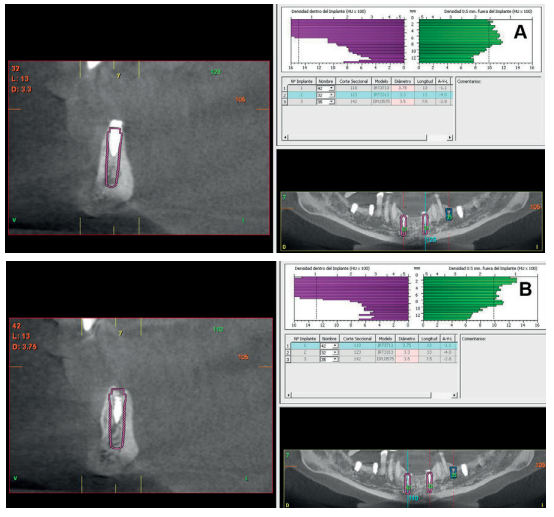

Aft er 4 years, the second and third quadrant molars began to have excessive mobility and serious periodontal problems, so it was decided to remove them and regenerate the alveoli with PRGF-Endoret. Once the area was regenerated (a month and a half later), a conebeam was performed to evaluate the residual bone volume. It can be seen how there was an uneven bone crest with areas of 3.3 mm in height up to a maximum of 7 mm (Figures 9 and 10). On this occasion, due to the protocol change described above, we opted for the direct insertion of extra-short implants, since the surgical protocols to address this type of situation in 2011 varied substantially, with these implants being a first-line tool for the treatment of this type of atrophy (Figure 11). Two extra-short implants were selected (5.5 mm diameter x 6.5 mm length for tooth 26, and 6 mm diameter x 5.5 mm length for tooth 27).